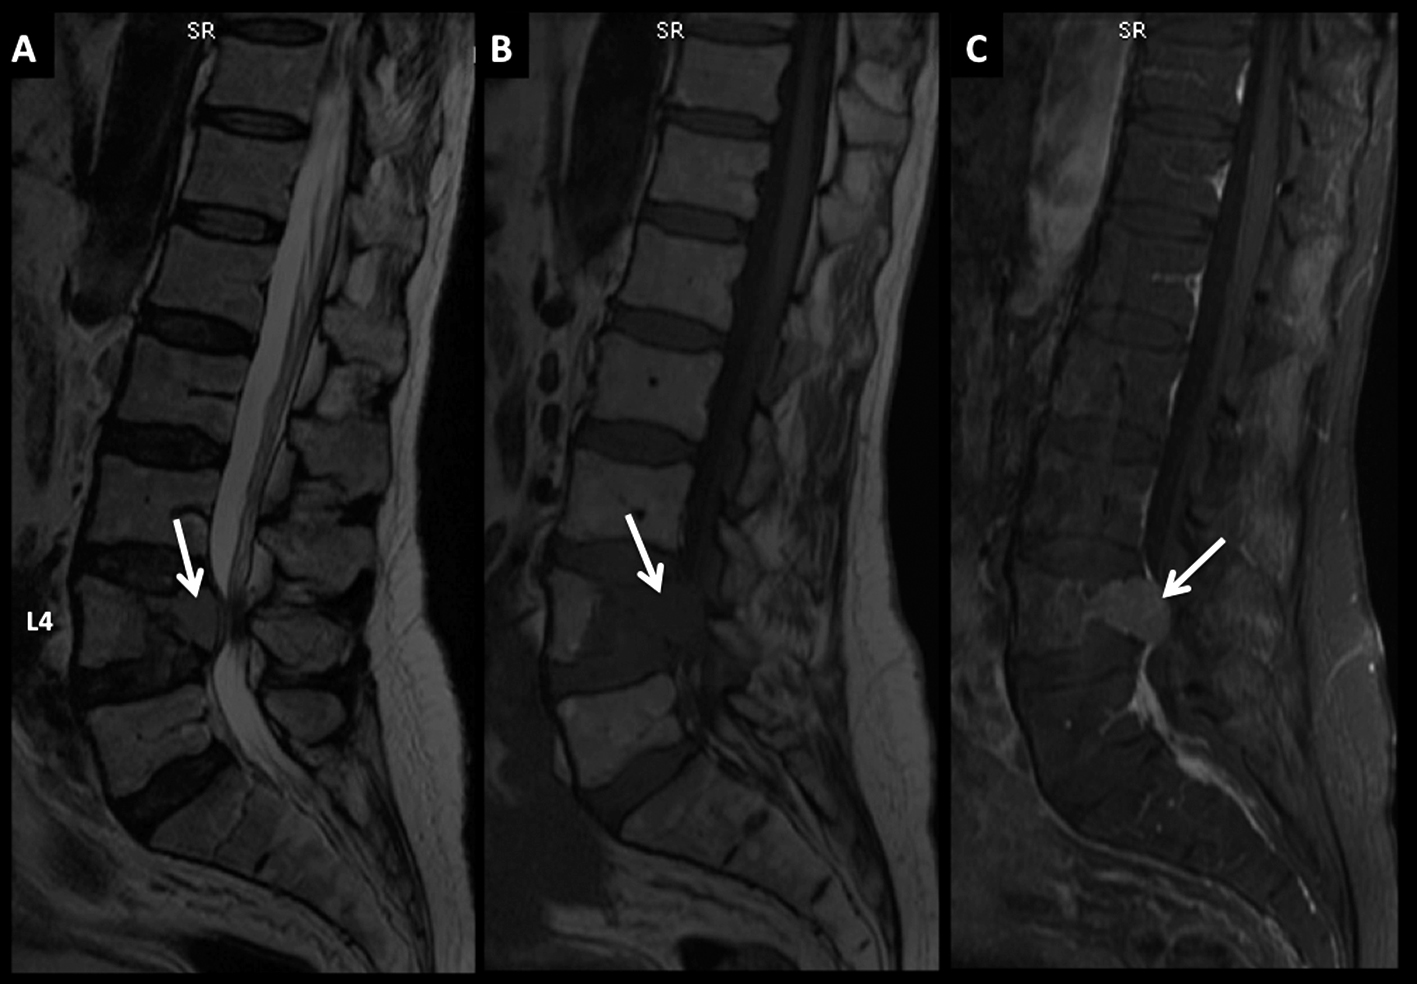

Figura 4

LNH, lesiones óseas y masa extradural, compromiso secundario.

Paciente con LNH sistémico, que presenta dolores óseos progresivos y un síndrome de medular asociado.

En RM, secuencia T2 sagital (A) se observan múltiples pequeñas lesiones óseas (*) heterogéneas, y una masa de partes blandas a nivel dorsal bajo, intra-raquídea, extradural, de baja señal en T2 con desplazamiento y compresión del cordón medular (flecha discontínua).

En secuencia T1 (B) es de baja señal y luego de administrar contraste presenta intenso realce, homogéneo (C).

LNH, lesiones óseas y masa extradural, compromiso secundario. (cont)

En el plano axial (D secuencia T2, E secuencia T1 y F secuencia T1 con contraste) se observa la masa descrita con un patrón de crecimiento que lo “amolda” al canal y se extiende a los espacios vecinos a través de los neuro-forámenes del nivel seleccionado.

Figura 5

LNH, lesiones óseas múltiples y masa intrarraquídea extradural, compromiso secundario.

Paciente con diagnóstico de LNH sistémico y lesiones óseas múltiples (*) a nivel dorsal bajo y masa intrarraquídea extradural con compresión medular.

Las lesiones son de baja señal en T2 (A) y T1 (B) con edema óseo en STIR (C) y realce intenso, algo heterogéneo con el medio de contraste (D).

La masa intrarraquídea es sólida con intenso realce y que comprime el cordón medular. En secuencia T1 en fase (E) y fuera de fase (F) se observa el comportamiento habitual de las lesiones agresivas, con aumento de señal en el pasaje de una fase a la otra. En difusión b1000 (G) y mapa de ADC (H) las lesiones son de alta y baja señal respectivamente, un elemento habitual en lesiones agresivas.